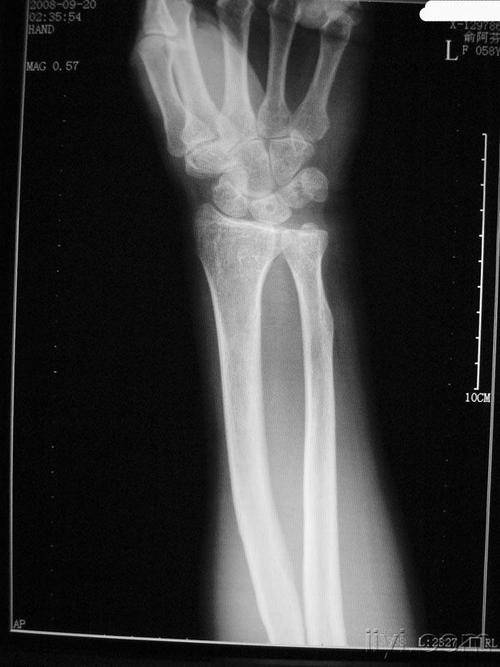

下尺桡关节位置图,桡尺关节位置图

下尺桡关节脱位的诊断和治疗

由 a data-lemmaid="1657254">桡骨 /a>下端腕关节面和尺骨下方的关节

下尺桡关节损伤

少见下尺桡关节掌侧脱位二例

下尺桡关节脱位

下尺桡关节半脱位

下尺桡关节

下尺桡关节分离